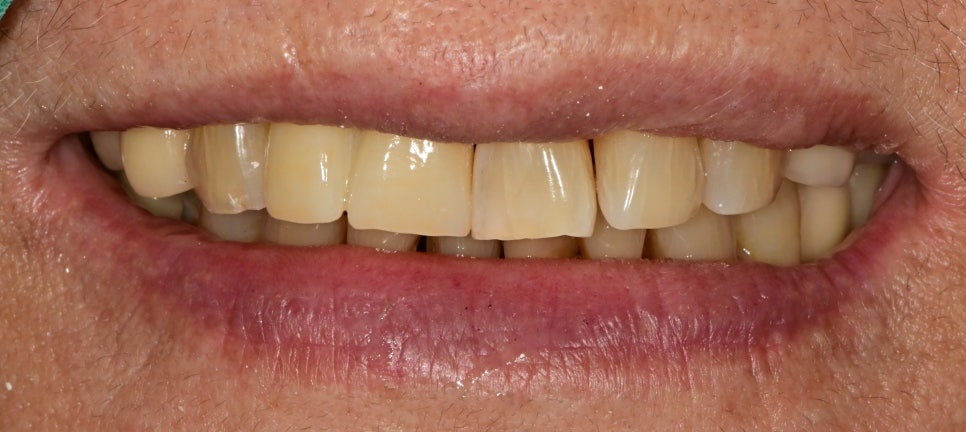

웃을 때 모습은 빈 공간이 거의 보이지 않고 자연스러운 것을 확인할 수 있습니다

기존 치아들의 마모되고 부분적으로 깨진 부분들과 비슷하게 보이기 위해

보철물의 형태도 자연스럽게 제작하기 위해 노력했습니다

이번 케이스는 간단한 레진만으로 눈에 띄는 변화와 만족감을 가져올 수 있었습니다